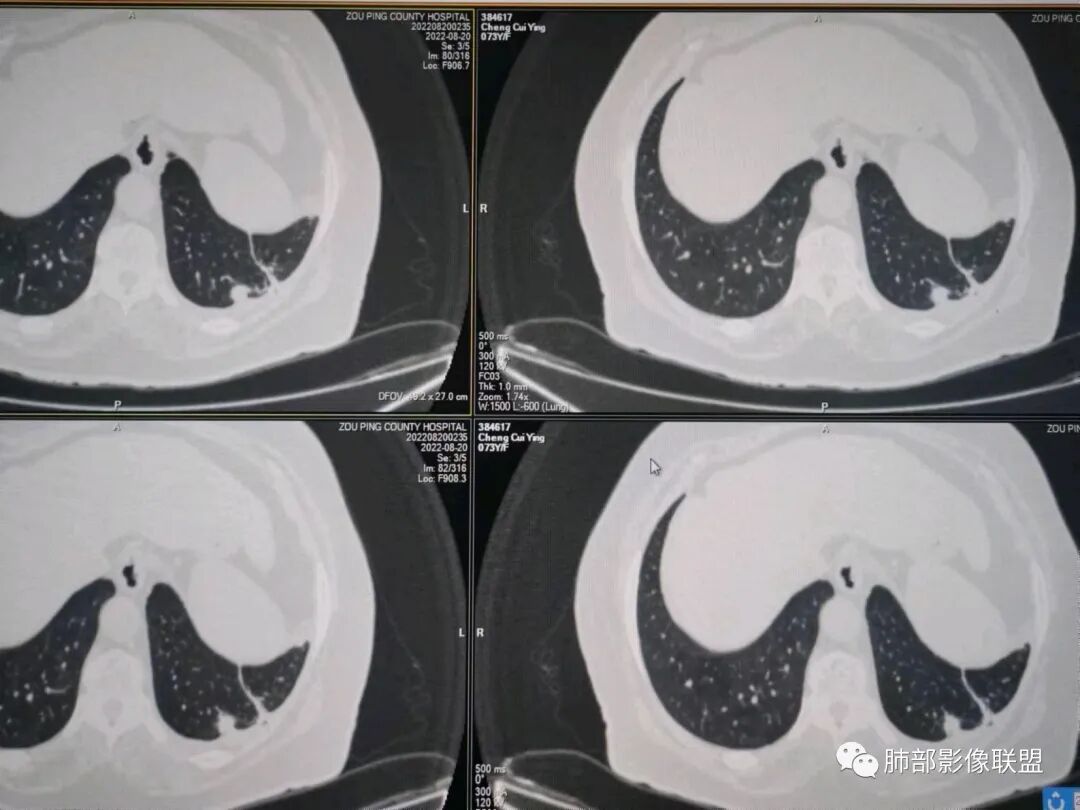

秦化君:左肺下叶外基底段胸膜下软组织密度结节性,边缘毛糙与血管相连,密度不均,增强后病灶内边界不清低密度区,胸膜栽桩,少量胸腔积液。考虑恶性病变,腺癌可能。真菌待排。

谢加平:老年女性,慢性咳嗽,咳白痰史,左肺下叶后基底段胸膜下肿块,类圆形,边界清膨隆,密度不均匀,低强化及小灶性坏死,坏死轮廊不清,胸膜下栽赃明显,左侧胸腔少量积液,向胸壁肌侵犯,另肿块近心侧见支指套征,粘液低密度,支持恶性,粘液腺Ca,经皮肺穿刺活检明确诊断。

361度:老年女性,发热,胸部CT示左下肺胸膜下结节影,血管集束,毛棘,密度不均,胸膜栽赃,少量胸腔积液,不均匀强化,坏死边界不清,肿标轻微升高,考虑恶性,鳞癌合并感染。

红星:老年女性患者。胸膜下结节病变,明显的膨胀,并局部侵犯胸膜,增强明显的强化。病灶周围带有局灶的渗出性改变以及条索上的影。考虑腺癌的可能性大,鉴别结核肉芽肿性病变。

春秋:左肺下叶胸膜下结节,边缘平直,内见低密度区,胸膜下胸腔积液相隔,考虑炎性结节可能性大,伴小脓肿形成。

宇宙:左肺下叶胸膜下球形肿块,边界尚清,局部平直,局部膨隆,内侧缘长索条,胸膜栽赃,轻度不均匀强化,其内坏死边界欠清,左侧胸水,考虑腺癌,鉴别放线菌。

党医生:左下肺结节,整体呈不完全规则、局部呈球形结节,有较长、轻大的条索壮改变,球形病变区域与胸膜呈宽基底,密度不均匀、有液化低密度区,不均匀强化,总体分析考虑:结核可能大,其次炎性假瘤,肺癌可能小。

摘星空竹子:左肺下叶后基底段与外基底段交界处胸膜下椭圆形软组织肿块,边界尚清,密度欠均匀,患侧少量胸腔积液,增强扫描轻度或无强化,肿块中央可见斑片状低密度区,边界尚清,考虑OP伴脓肿或结核,鉴别腺癌。

李庆东:左肺下叶外基底段胸膜下球形软组织密度,边缘毛糙与血管相连,轻度强化,增强后病灶内边界不清低密度区,宽基底于胸膜,少量胸腔积液。考虑良性病变,炎性假瘤可能大。特殊感染待排,鉴别腺癌。

袁媛:左肺下叶胸膜下球形肿块,宽基底连于胸膜下,胸膜栽赃,边缘膨隆,有血管供应,增强有强化,考虑腺癌。

gaoql:倾向肿瘤,胸膜下脂肪间隙受累,有细角和nse升高,如果男性,要考虑鳞癌,但是个女性,还是先考虑腺癌的可能。感染指标升高,还需鉴别炎性肉芽肿性病变,能累及胸膜下间隙的,要鉴别脓肿或放线菌。

看图说话:胸膜下肿块,密度不均,边缘毛糙,增强后不均匀强化,胸膜栽赃,左侧胸腔积液,腺癌,鉴别肉芽肿。

songml:老年女性,反复咳嗽咳痰胸闷4年,加重伴发热一周。左肺下叶后基底段胸膜下肿块影,密度较均匀,边缘较清,侵及胸膜下脂肪间隙。考虑恶性病变,腺癌可能,鉴别真菌感染。

人生海海:左肺下叶不规则形软组织密度影,膨隆生长,边缘清楚,分叶,棘突征,支气管截断,血管纠集,病灶轻度强化、内多发坏死,左侧少量胸腔积液,考虑粘液腺癌,鉴别肺脓肿。

位移:老年女性,左肺下叶肺胸膜下团块影,边界清、毛糙,膨隆,内密度不均,不均匀强化,内见坏死,胸膜栽赃,胸腔少量积液,首先考虑恶性肿瘤,低分化腺癌,鉴别小细胞癌,炎性假瘤。

赖晓宇:膨隆,浅分叶,支气管截断,内部坏死边界不清,胸膜受累,胸腔积液,考虑恶性。

枷黎:左肺底类圆形结节,略分叶,毛刺不明显,周围似乎有淡淡的晕,增强扫描呈较均匀轻度强化。结合临床症状和实验室检查,首先考虑炎性肉芽肿类病变可能,肿瘤待排。

赵:增强病变与胸膜分界清晰,平扫密度左侧胸腔密度高能否是慢性炎症刺激引起,坏死边缘清晰,提示病变强化明显。临床实验室检查血象增高先考虑慢性炎症,腺癌待除外。

许慧良:老年女性患者,左肺下叶后基底段胸膜下结节影,边界清楚,密度不均匀,内部有低密度影,边缘有结节颗粒感,对胸膜有黏连牵拉感,考虑恶性,腺癌可能。

王静:左肺下叶病变,紧贴胸膜,楔形,尖端朝向肺门,临近胸膜未见明显增厚,胸腔少量积液,增强扫描病变内部不均匀强化,可见边界相对清晰液化坏死区。患者有发热病史,血象高。诊断,左肺下叶炎性肌纤维母细胞瘤可能,鉴别肉芽肿性病变。

梦妮6-1:老年女性,慢性咳嗽,咳白痰史,左肺下叶后基底段胸膜下肿块,类圆形,边界清膨隆,密度不均匀,中间有低强化及小灶性坏死,边界清,有胸水,病肺门侧有支管通过,胸膜界线清,考虑良性病可能。隐球菌?

WXD:左肺下叶胸膜下占位性病变,整体强化还是比较明显,中心坏死边界较清晰,还是先考虑炎性肉芽肿性病变,鉴别炎性肌纤维母细胞瘤。

良孑:左肺下叶胸膜下结节,可见晕征及软毛刺,边缘有锯齿状浅分叶,其内坏死边界不清,均匀性低强化,局部层面边缘可见平直及u型凹陷,胸膜糊墙并少量积液,慢性病史急性发作,炎性标志升高,首选炎性肉芽肿性病变,0P并脓肿,高龄,有锯齿状浅分叶腺癌也难以除外。

瑞欣:左肺下野胸膜下高密度灶,边界较清,宽基底与胸膜相贴,胸膜增厚,强化可见病灶内低密度区坏死区,胸膜没有栽赃,首选考虑炎性肉芽肿,鉴别腺癌。

笑微微:左肺下叶外后基底段见结节影,密度不均,边缘欠光整见浅分叶及棘样突起,病灶与相邻胸膜分界不清并见胸膜不均匀性增厚,增强呈不均匀强化,左侧见少量积液。考虑腺癌,鉴别结核。

放射线:左肺下叶后基底段胸膜下肿块,边缘膨隆,密度不均匀,内见低密度坏死,胸膜栽赃,左侧胸腔少量积液,考虑恶性,腺癌?鉴别放线菌,OP伴脓肿。

仲夏:老年女性,咳嗽咳痰近4年,左肺下叶胸膜下类圆形肿块,内侧绳索征,内部密度不均匀,可见坏死,周围小空泡,小叶间隔增厚,胸膜下积液,轻度强化,NSE、细胞角蛋白酶19片段高,考虑恶性肿瘤,腺癌?

许慧良:老年男性患者,左肺下叶后基底段胸膜下结节影,边界清楚,密度不均匀,内部有低密度影,边缘有结节颗粒感,对胸膜有黏连牵拉感,考虑恶性,腺癌可能。

AAA张春雨:左肺胸膜下大小不等的多发病灶,内有支气管半进入征,强化内部不均,患者有明显肺气肿背景,胸阔呈桶状,少量胸腔积液,综合考虑隐球菌感染的可能性最大,鉴别腺癌。